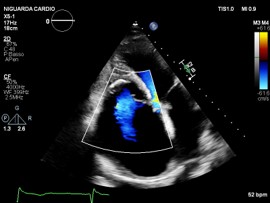

We report the case of a 48-year-old male with chronic eosinophilic leukaemia (CEL) complicated by multiorgan damage, including chronic kidney disease (CKD) and liver disease with recurrent ascites. Cardiac follow-up began at CEL diagnosis. The patient remained stable until 2015, when he underwent two atrial tachycardia ablations. Cardiac magnetic resonance imaging suggested Loeffler endocarditis, showing right ventricle (RV) fibrosis, mildly impaired RV systolic function and severe tricuspid regurgitation (TR). The left ventricle (LV) remained preserved. Cardiac computed tomography excluded coronary disease. In June 2025, despite guideline-directed medical therapy, the patient developed severe dyspnea, massive ascites and acute kidney injury on CKD. Transthoracic (TTE) and transoesophageal echocardiography showed torrential TR not amenable to percutaneous repair. Laboratory results showed normal blood count, serum creatinine 5.5 mg/dL, bilirubin 2 mg/dL, NT-proBNP 7950 pg/mL. Electrocardiography showed junctional rhythm. On admission, intravenous furosemide was continued. A 5-L paracentesis yielded negative cytology and microbiology. TTE confirmed severely dilated RV and atrium, paradoxical septal motion, hypokinetic RV and torrential TR. LV function was normal. Right heart catheterization revealed reduced cardiac index (2.04 L/min/m²), mildly elevated pulmonary capillary wedge pressure (14 mmHg), normal pulmonary pressures (24/15/19 mmHg), normal pulmonary vascular resistance (1.3 WU) and elevated right atrial pressure (19 mmHg). Low dose dopamine (2 mcg/kg/min) improved perfusion and diuresis, leading to clinical stabilization with weight loss (−19 kg), waist reduction (−11 cm), and improved labs. Multisystem evaluation was undertaken. Portal hypertension and decompensated liver disease were excluded. Liver biopsy revealed extensive fibrosis without cirrhosis or malignancy. MELD-XI was 48. Haematology confirmed longstanding CEL remission. Imatinib was discontinued, with monthly molecular monitoring. Renal function normalized under inotropes, with no further tests needed. Extracardiac and serologic workup was negative. Blood type: B Rh+. The case was reviewed by the transplant team. No absolute contraindications to heart transplantation were found. Combined heart–liver transplantation was deemed unnecessary given the absence of cirrhosis. LVAD was excluded. On August 1st, 2025, the patient was listed for urgent heart transplantation (Urgency level 2).